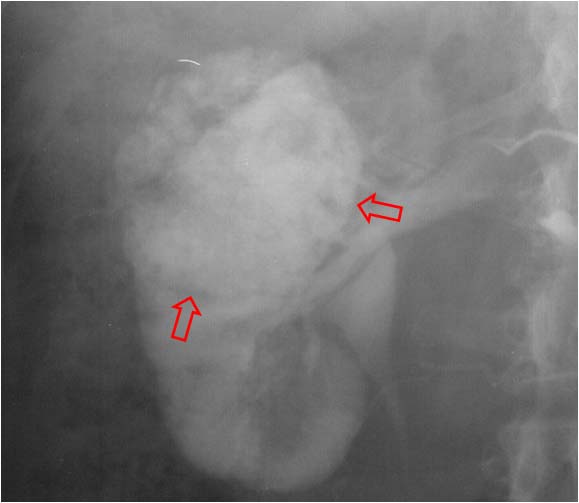

SIGNO DEL BORDE o SIGNO DEL ANILLO HIDRONEFRÓTICO

borde uro

Signo de obstrucción renal en la urografía intravenosa, más frecuente en la uropatía obstructiva crónica. Consiste en el delgado anillo de parénquima renal opacificado que rodea el sistema pielocalicial dilatado, dando un aspecto de pielograma negativo.

Aunque en el caso presentado, el estudio no es una urografía sino una arteriografía, el signo es similar. Vemos una delgada capa de parénquima (flecha) que rodea a los cálices dilatados, en esta fase aún no opacificados.

No debe confundirse este signo con el Signo del borde, aunque tienen semejanzas. En los dos se produce un adelgazamiento de la cortical renal: en el signo del borde está causado por hidronefrosis; en el signo del borde fino se origina por la presencia de una o más masas renales. Tampoco hay que confundirlo con el Signo de los anillos de Dunbar, aunque ambos se ven en la hidronefrosis. El anillo hidronefrótico es el realce cortical mientras que los anillos de Dunbar corresponden al contraste en los túbulos renales.